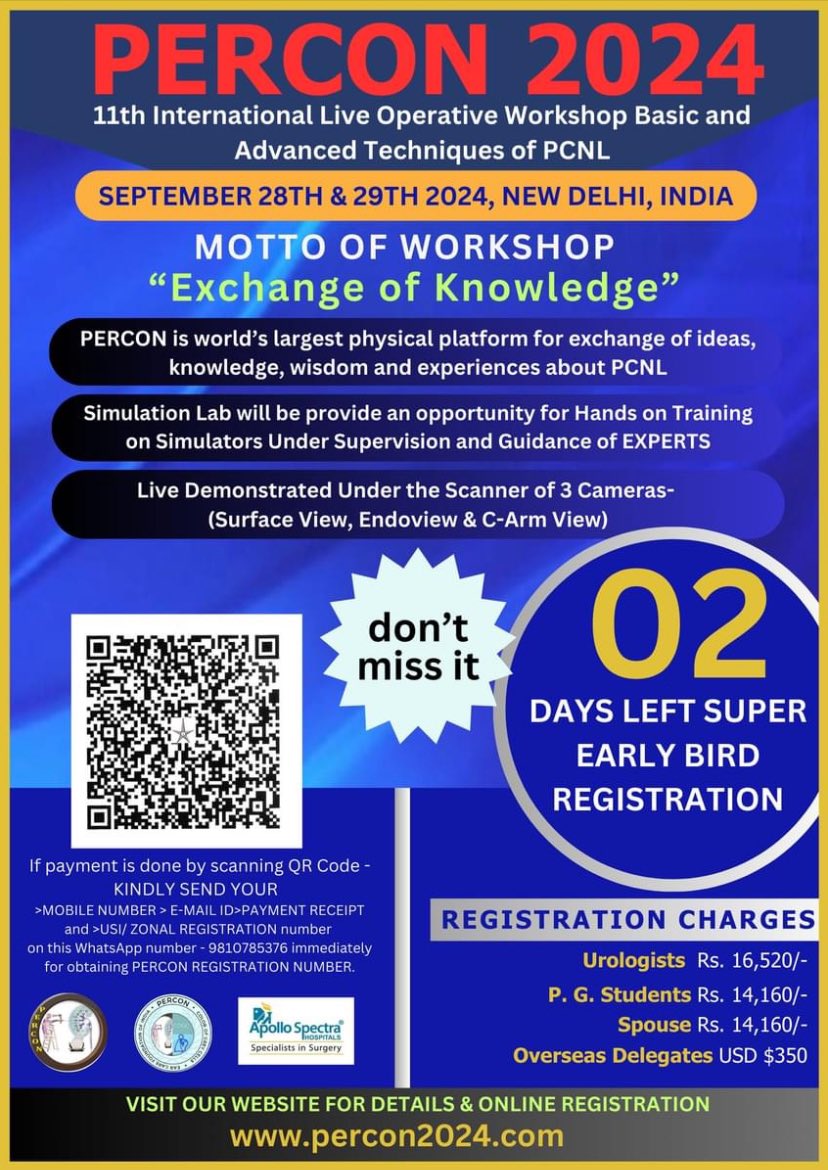

Get ready for PERCON 2024.. The largest event focussed on PCNL worldwide.. every aspect of PCNL is discussed threadbare.. Shashi Kiran Pal Endourology Academy Dr Ashish Rawandale Patil Dr Avreen Singh Shah MCh MS mohamed elshazly Dr Vaddi Chandra Mohan Karthickeyan N 𝘿𝙚𝙚𝙥𝙖𝙠 𝙍𝙖𝙜𝙤𝙤𝙧𝙞 Abhay Mahajan Dr. Pankaj N. Maheshwari